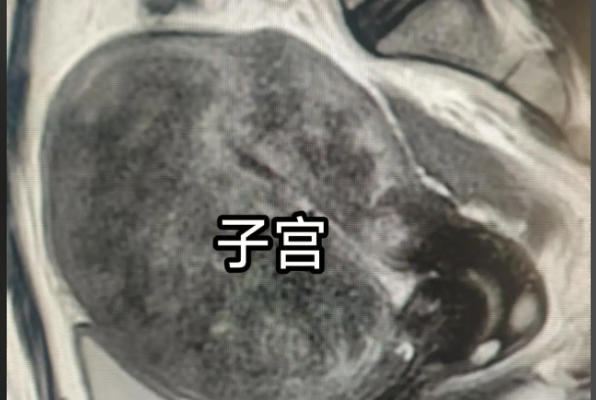

子宫萎缩是指子宫体积缩小、组织变薄及功能减退的一种生理或病理状态,通常与雌激素水平下降密切相关。作为女性生殖系统的核心器官,子宫的健康状况直接影响整体生理功能与生活质量。从医学角度来看,子宫萎缩可分为自然性与非自然性两类:自然性萎缩多见于绝经后女性;而非自然性萎缩则可能由过早卵巢衰竭、手术、放疗或长期药物抑制等因素引发。子宫萎缩对女性的影响是多维度的,除了生理上,心理上的也要引起充分重视。

雌激素就像子宫的“营养剂”,维持着子宫内膜的厚度、肌层的弹性以及宫颈的润滑状态。当雌激素水平下降,子宫组织逐渐失去支撑,体积缩小、血流减少,从而引发一系列连锁反应。此外,雌激素减退还会加速骨质流失,增加骨质疏松风险。

总的来说,子宫萎缩对女性的影响是全面而深远的,从直接的生殖功能减退、泌尿问题和性健康困扰,到长期的骨质疏松、心血管风险上升及心理压力,构成了一个复杂的健康挑战。然而,重要的是区分自然萎缩与病理性萎缩:前者是生命过程的正常部分;后者则需积极医疗干预。